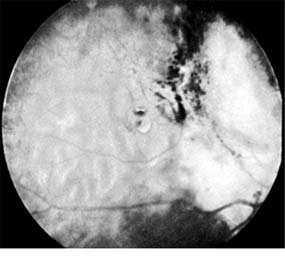

Astrocytic (Glial) Hamartomas

Astrocytic hamartomas are translucent to whitish retinal and optic nerve head tumors most frequently associated with tuberous sclerosis (Bourneville's disease) (Figure 10-31). They may also be associated with neurofibromatosis-1 and -2 or may occur as isolated findings. These tumors are congenital. They may grow slowly and, as they mature, become calcified, acquiring a mulberry configuration.

Figure 10-31

Figure 10-31: Retinal astrocytic hamartoma.